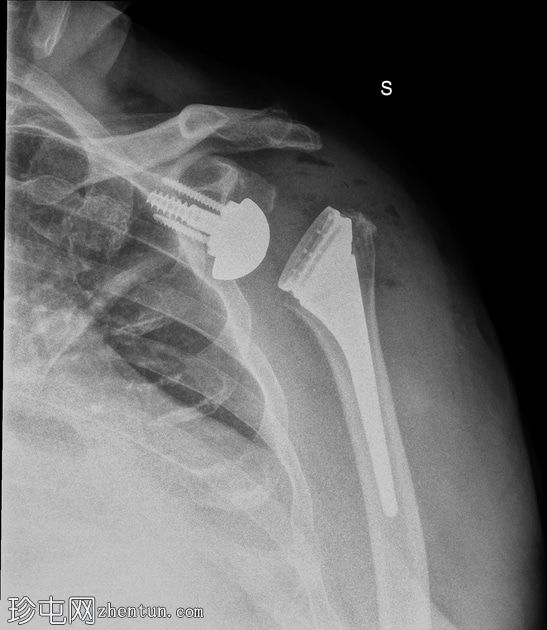

侧面

胸部侧面图:肱骨假体前脱位,盂球固定到位。和纵隔正常。无胸腔积液。

全肩关节置换术后肱骨假体前脱位,伴假体分离。